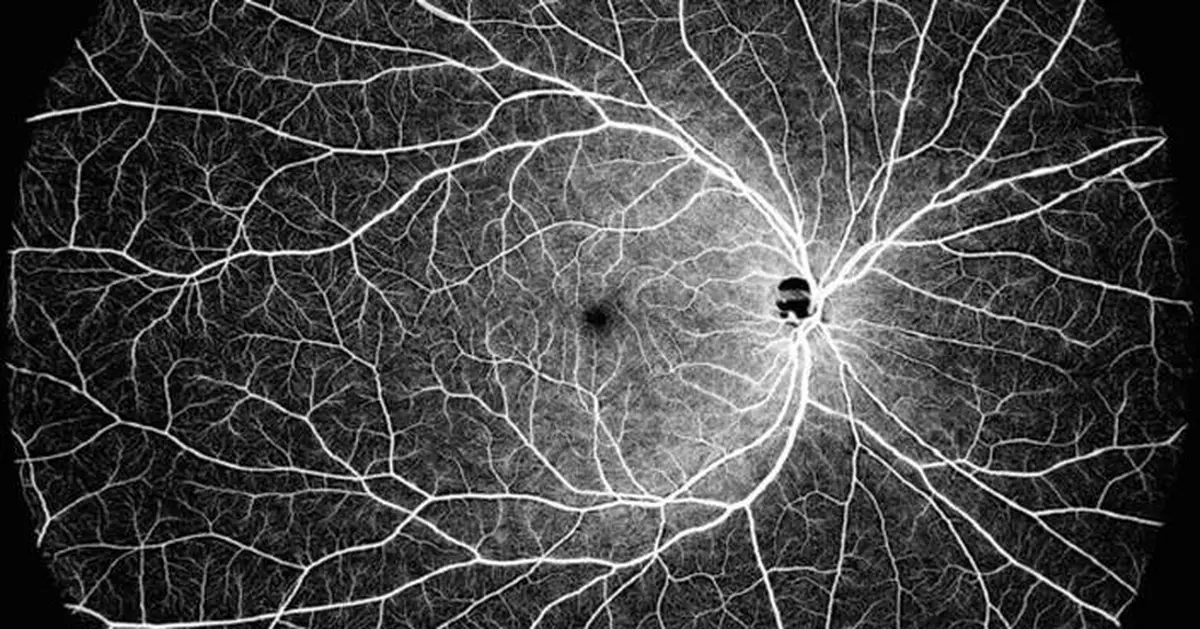

DREAM OCT is able to cover an ultrawide field single scan which delivers a 130° OCTA image. DREAM OCTâ„¢ swept-source 12 mm super-depth scanning allows superior imaging of the choroid and retina, and a large portion of the vitreous space. The super-depth anterior scanning capabilities achieves 16.2 mm (in air), allowing for the complete anterior segment from the cornea to the anterior part of the vitreous to be scanned in only one scan. The longer wavelength allows for superior penetration through opacities in either lens or vitreous.